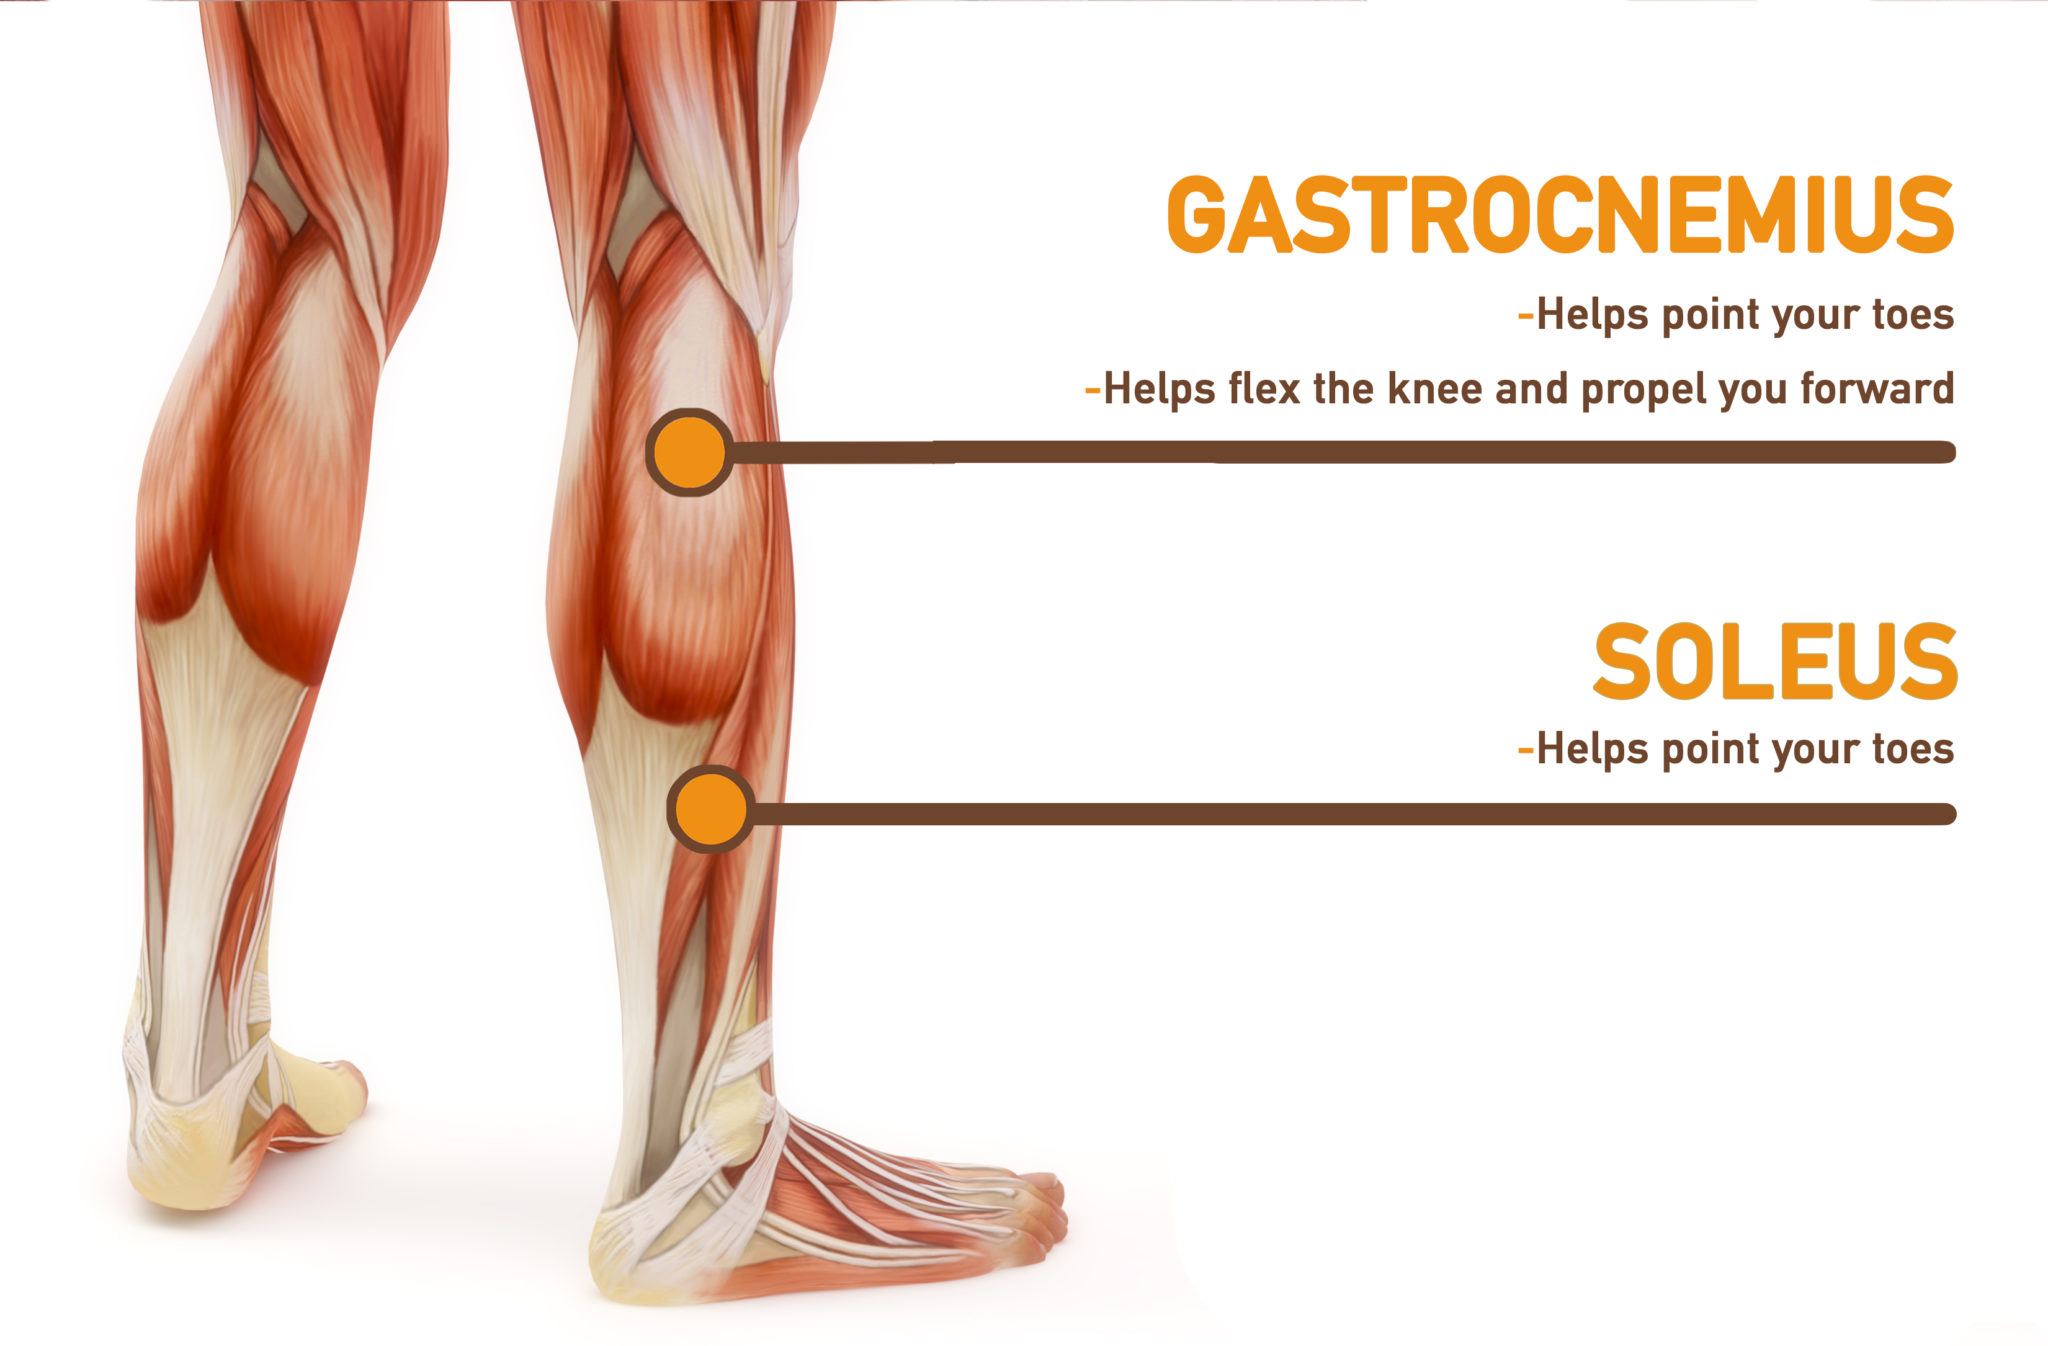

Anatomy

| Function | Talocrural joint: Foot plantar flexion Knee joint: Leg flexion |

Soleus

| Function | Talocrural joint: Foot plantar flexion |

Gastrocnemius Stretches

Soleus